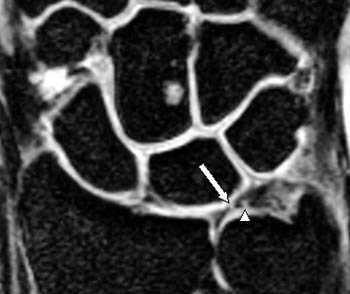

(Слева) Непрямая МР-артрография в режиме Т2 ВИ FS, коронарный срез: визуализируется травматический разрыв ТФХК, проявляющийся отрывом волокон от ямки и шиловидного отростка с появлением жидкости во влагалище сухожилия ЛРЗ.

(Справа) Непрямая МР-артрография в режиме Т2 ВИ FS, аксиальный срез, этот же пациент: на ладонной поверхности запястья определяется синовиальная киста в Отмечается наличие жидкости во влагалище сухожилия ЛРЗ. (Слева) Рентгеноскопия, передне-задняя проекция: визуализируется поступление контрастного препарата в ДЛЛС через центральную часть ТФХК, что свидетельствует о глубоком разрыве последнего.

(Справа) МР-артрография в режиме Т1ВИ FS, коронарный срез: наблюдается разрыв центральной мембранозной части ТФХД. Контрастный препарат распространяется в ДЛЛС. Дефект в данном месте обычно возникает вследствие дегенеративного процесса. (Слева) МР-артрография в режиме Т1ВИ FS, коронарный срез: отмечается, что распространение контрастного препарата ограничено лучезапястным суставом, а верхний край ТФХК имеет ровный контур. Пациент жалуется на боли с локтевой стороны запястья после падения.

(Справа) МР-артрография в режиме Т2ВИ FS, коронарный срез, этот же пациент: визуализируется неровный контур глубокого слоя ТФХК, обусловленный его разрывом. В ДЛЛС видна собственная жидкость, а не контрастный препарат, поскольку она характеризуется гипоинтенсивным сигналом на Т1 ВИ.